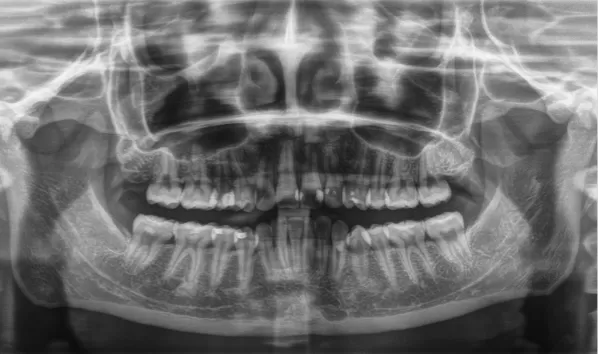

Rayons X avant le traitement

[Radiographie panoramique/Céphalogramme latéral]